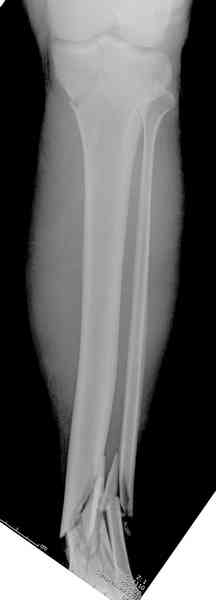

При высокоскоростных переломах редко можно встретить изолированную травму пилона, и в моей практике изолированные травмы большая редкость, поэтому, как дополнение к обсуждаемой теме, решил представить свежий, двухдневной давности случай.

Предыдущей сменой до 4:00 утра по поводу открытого перелома бедра, тибиал плато, пилон и надколенника сделана операция.

Пострадавшему 21 г., травма скоростная, после I&D с расширением раны, на бедре сделана операция ретроградным интрамедуллярным штифтом, остеосинтез с частичной резекцией надколенника и ушивание собственной связки.

На голень наружный фиксатор, рану на бедре ушили (рана была изнутри кнаружи всего 2 см). По протоколу травматических больных, до операции обследован ангиографически, (у больного дистально не смогли определить пульсацию) сосудистый хирург подтвердил проходимость на всем протяжении магистрального сосуда нижней конечности по снимкам ангиограмм.

В настоящее время больной в реанимации по поводу Черепно Мозговой Травмы и состояние улучшается. Запланировал ушивание раны в пятницу, если позволит состояние мягких тканей и при отсутстви отека возможно удастся просунуть перкутанномедиальную пластину.